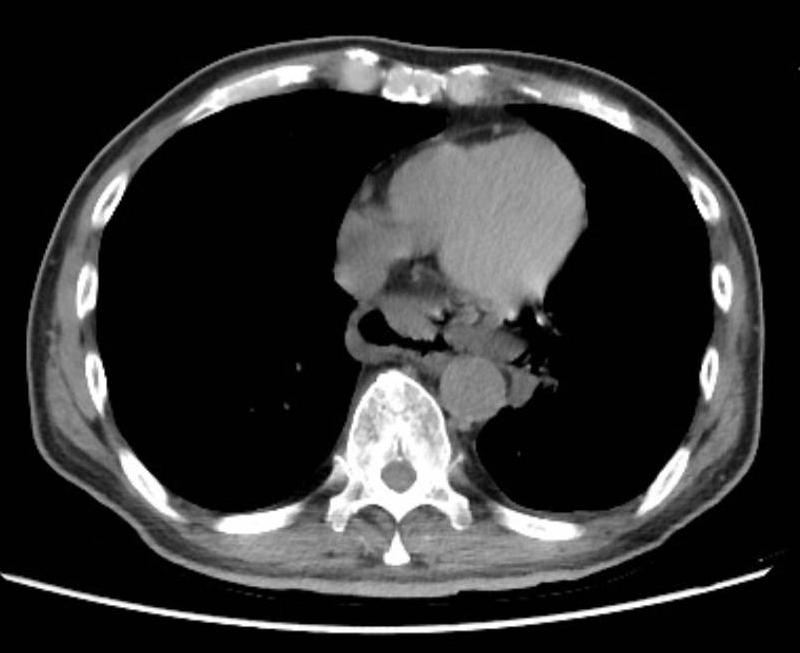

胸腔外科主任林鴻生指出,經電腦斷層(CT)檢查發現胃部因大量食物明顯脹大,併有遠端食道擴張,隔天胸部及上腹部持續疼痛,CT檢查又發現氣縱膈及雙側肋膜積水,胃極度脹大,診斷為「自發性食道破裂及左側膿胸」,由於情況危急,立即進行手術修補食道撕裂傷,並去除左側胸腔外漏食物殘渣,還作空腸造口,術後轉加護病房治療觀察。

老張在加護病房期間接受抗生素治療膿胸及縱膈腔炎,並以空腸造口灌食提供營養。經過三周積極治療下病況逐漸穩定好轉,移除呼吸器後轉一般病房治療照護一周後順利康復出院。(圖片說明:CT顯示遠端食道裂傷。